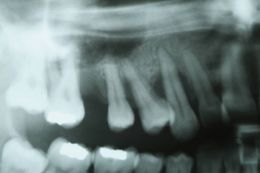

Questa giovane paziente giunge alla mia osservazione con gli elemnti 13, 14, 15, 16 gravemente compromessi da un punto di vista parodontale. Programmo l'estrazione degli stessi, attendo circa 3 mesi e poi provvedo dopo le indagini radiografiche e cliniche del caso al posizionamento di 4 impianti con rialzo verticale tramite griglia in titanio e rialzo del seno mascellare. Dopo nove mesi inizia la fase protesica: prima i provvisori e poi le corone in oro ceramica.

Aprile 2008 si posizionano gli impianti e griglia in titanio per un rialzo osseo verticale e rialzo del seno mascellare.